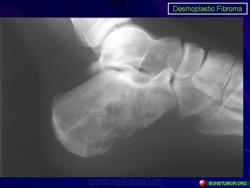

Десмопластическая фиброма редкая локально агрессивная внутрикостная опухоль, характеризующаяся продукцией опухолевыми клетками пучков коллагеновых волокон. Встречается в любом возрасте (чаще у лиц моложе 30 лет), с равной частотой у мужчин и женщин. Локализуется в основном в эпифизах и метафизах длинных костей (бедренная, плечевая, большеберцовые кости), плоских костях (кости таза, лопатка), нижней и верхней челюстях.

Рентгенологически остеолитический очаг, вызывающий вздутие истончённой кортикальной пластинки.

Десмопластическая фиброма